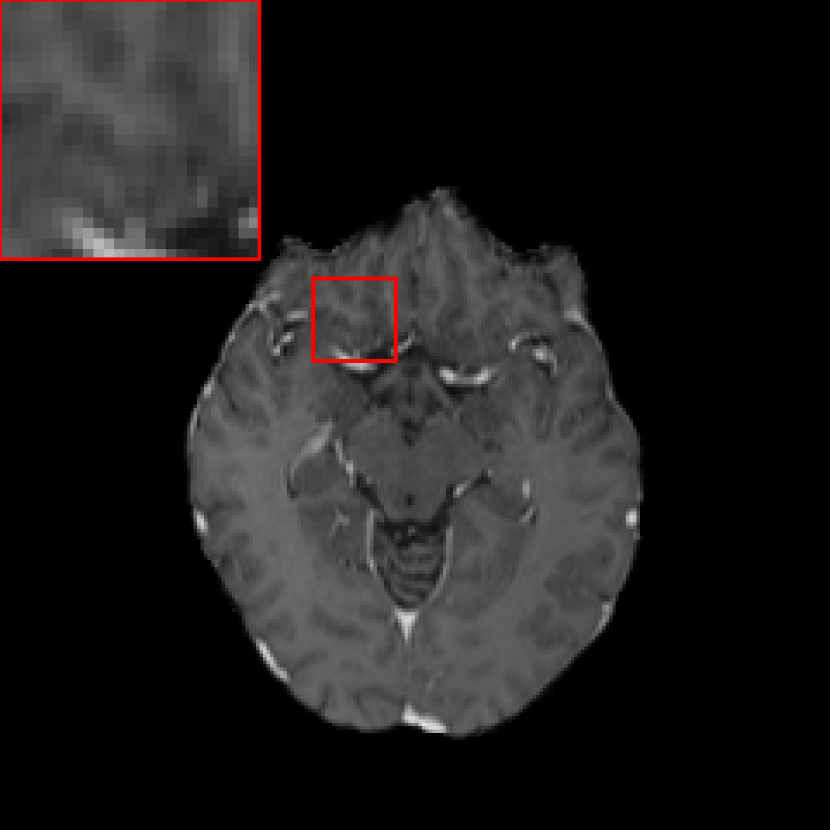

Figure 2: Exemplary images acquired from different time points: (a) temporal prior image; (b) current main image, where the contour indicated by the arrow is segmented incorrectly as a metastasis by a neural network that used the prior image as an additional channel as opposed to an additional pathway; (c) difference between (a) and (b), where the bright region indicated by the arrow is the main cause for the incorrect segmentation.

In contrast-enhanced MRI images with 3D volumetric gradient echo imaging (e.g., BRAVO, GE Healthcare; MPRAGE, Siemens Healthcare; 3D TFE; Philips Healthcare) 36, many structures such as blood vessels are also enhanced by contrast agents. Hence, they have similar appearance to metastases in the regard to intensity, shape, and size in 2D intersectional planes. As a consequence, it is very challenging for human experts to distinguish them. BM differ from blood vessels in several aspects. One is that although they appear similar in 2D intersectional planes, they have distinct morphological appearance in 3D space. For example, enhanced vascular structures are tube-like structures with bifurcations, while the majority of BM are sphere-like structures 37. Therefore, 3D neural networks are advantageous over 2D networks to extract 3D features. In addition, BM have relatively larger morphological changes over time than normal tissues. Without treatment BM volume size typically grows faster than normal tissues due to the high proliferation rate of tumor cells. With treatment BM volume sizes change depending on treatment response, for example, volume size decreases in regression, increases in progression, and oscillates (increases first and later decreases) in pseudo-progression 38. In radiation therapy, patients have regular follow-up MRI scans in approximately every 4-6 weeks. Therefore, by comparing two images acquired from two time points, if a high contrast structure emerges or grows, this structure has high confidence to be a metastasis. To integrate such temporal prior information in deep learning, two potential ways are possible: using the temporal prior volume as an additional input channel or as an additional input path. As anatomical structures imaged at different time points cannot be perfectly registered to the same position, using temporal prior volumes as an additional channel will result in a high FP rate. An example is displayed in Fig. 2, where a normal tissue region indicated by the arrow in Fig. 2(b) is segmented incorrectly as a metastasis. Such mis-segmentation is mainly caused by the imperfect registration, since high intensity difference is observed in the corresponding region of the difference image (Fig. 2(c)). To avoid such problem, in this work we propose to put the temporal prior volume as an additional input path, where features from two time points are merged at deep layers. For distinction, the modified DeepMedic architecture is called DeepMedic+ in this work. The overall DeepMedic+ architecture is displayed in Fig. 3, where the normal resolution subvolumes from both the prior and main datasets as well as two low resolution subvolumes from the main dataset are fed into DeepMedic+. Note that for volumes without any temporal prior, an empty prior volume with zero values is used.